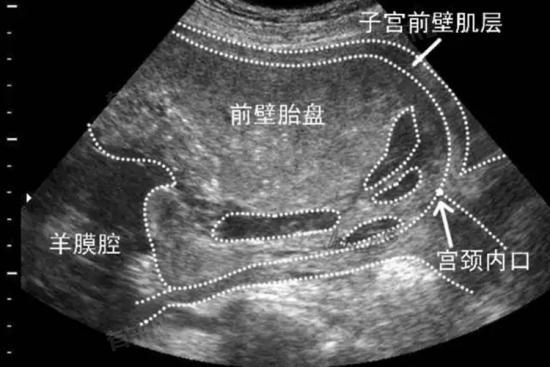

- 胎盘附着于子宫前壁或后壁均属正常解剖变异,其形成与受精卵着床时的子宫内膜状态相关。前壁胎盘指胎盘附着于子宫体前侧,后壁胎盘则附着于子宫体后侧,两者在妊娠期并发症发生率上无显著差异。

- 值得注意的是,胎盘位置与前置胎盘风险存在一定关联。胎盘附着于子宫下段或宫颈内口时称为前置胎盘,这与胎盘附着于前壁或后壁无直接因果关系。无论胎盘位于前壁或后壁,只要未覆盖宫颈口,均不构成剖宫产指征。